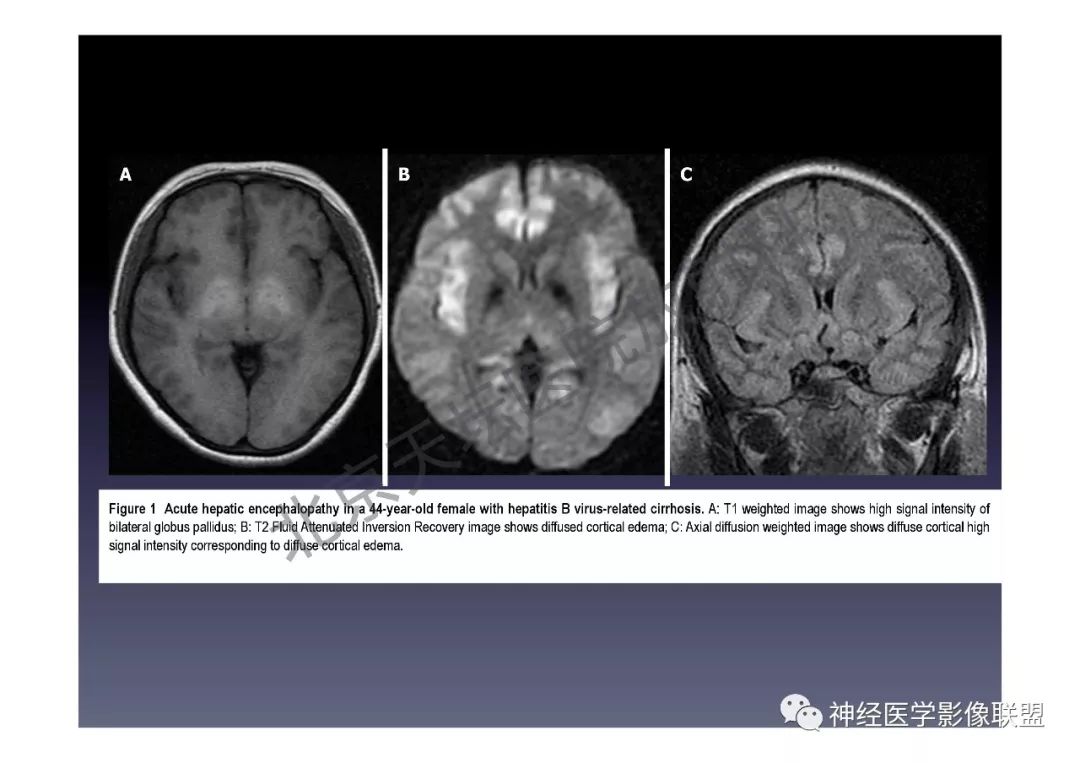

头颅磁共振dwi高信号一定就是脑梗死吗?